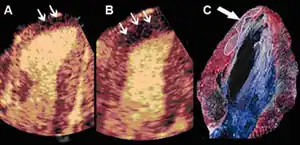

Infarct size determination

Adenosine infusion, can increase perfusional defect, as a result per an animal study indicates that "a better correlation between the echocardiographic measurements and the necrotic area determined by tissue staining". [39]